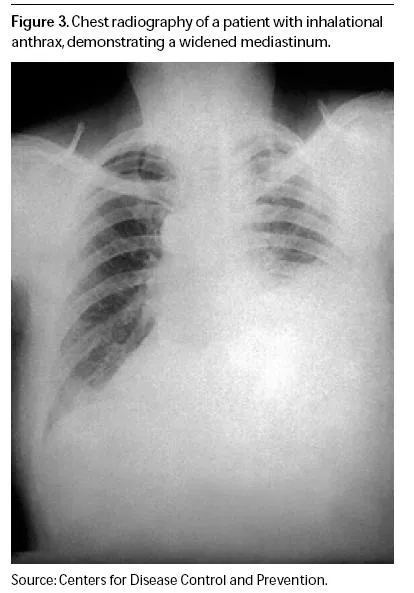

💡 Master This: Inhalational anthrax shows widened mediastinum in >90% of cases - any flu-like illness with mediastinal widening in multiple patients requires immediate bioterrorism response

| Anthrax | Widened mediastinum | 1-6 days | >80% | <24 hours | No |